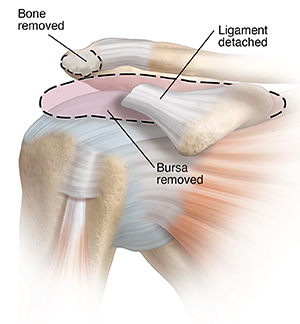

Impingement

Repeated overhead movements can inflame your rotator cuff and bursa. A bone spur may also form. This causes pain and problems with some arm movements. Impingement is also called bursitis or tendinitis.

During surgery, an inflamed bursa may be removed. Bone may be trimmed. And the ligament may be detached. These steps make more room. This eases pressure and lets the arm move more freely.